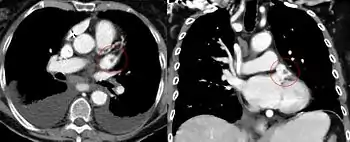

![]() الخِلْب[1] أو بالأحرى الخِلْبَان (الخلب الأيمن والخلب الأيسر) هما، في علم التشريح، لاحقتان متصلتان بالأذينين في قلب الإنسان والحيوانات الثديية. وهو يسمى أيضا لاَحِقَة الأُذَيْن[2] أو أُذَيْنَة الأُذَيْن.[2] يقع الخلب الأيمن بجانب الأبهر الصاعد ويقع الخلب الأيسر بجانب الجذع الرئوي (أي الشريان الرئوي الأصلي). المراجع